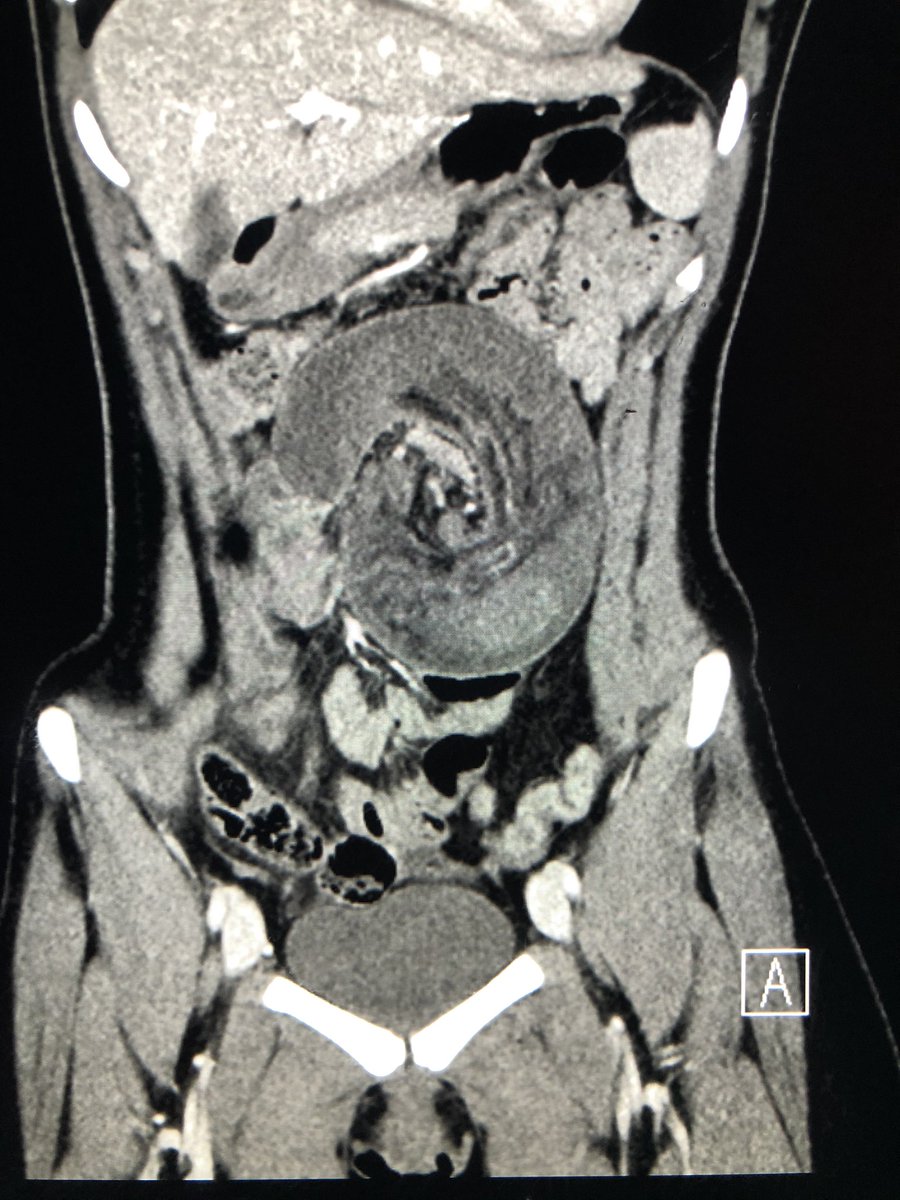

Classic! Care to guess what this appearance is pathognomic of?pic.twitter.com/11wHLxGGdr